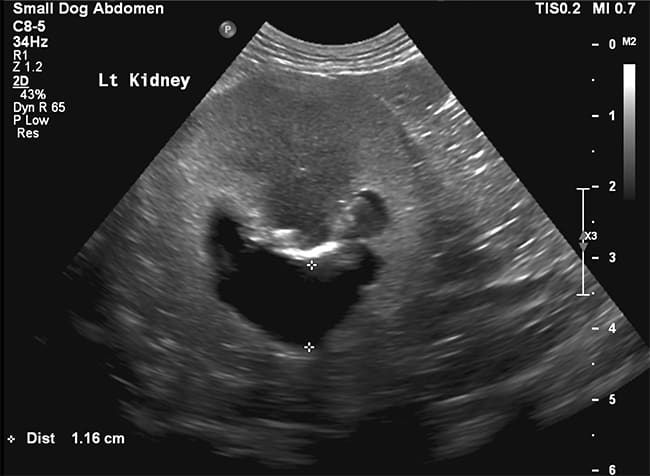

He was dehydrated on examination and also uncomfortable on palpation of his cranial abdomen. Initial diagnostics revealed a marked azotaemia (serum creatinine 500 umol/L, RI <140), therefore abdominal ultrasonography was performed to identify a potential underlying cause. Whilst his right kidney appeared small, fibrotic and likely end-staged, the left kidney was more appropriately sized but had significant pyelectasia (11 mm, RI < 2mm).